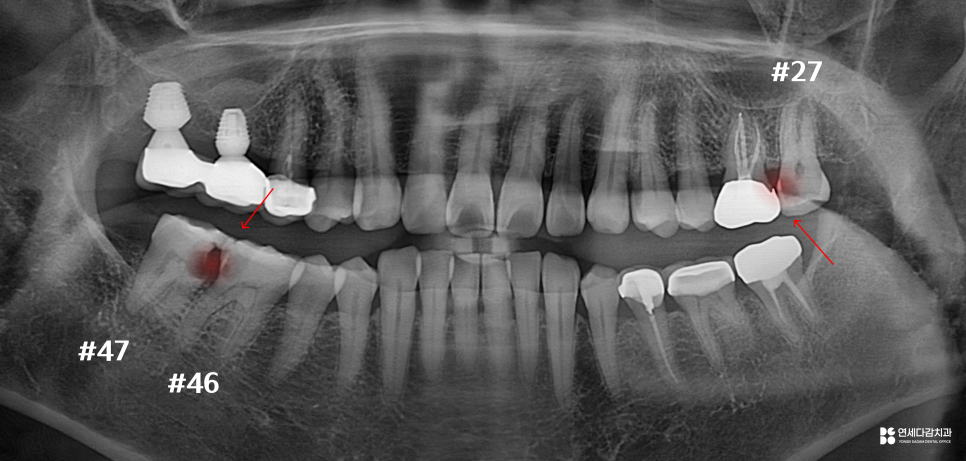

위아래 병변의 진행 정도를 살펴봤을 때,

47번은 이미 치근 부위로 확산되어 있습니다.

치근은 치조골 속에 위치하고 있어

병변에 접근하는 것이 매우 어렵습니다.

또한 치근이 손상되면 강도 자체가 저하되어,

저작압을 버티기 어려운 상태가 됩니다.

위와 같이 엑스레이에서도

병변이 명확히 확인할 수 있는 반면,

실제로 병변을 정리해 보기 전까지는

정확히 알 수 없는 부분도 존재합니다.

개롱역 치과 에서 설명해 드리는

대표적인 것이 신경 침범 여부입니다.

방사선 사진상으로

치수 근처까지 도달한 것처럼 보이더라도,

실제로 치수까지 이어졌는지는

직접 제거해 보아야 알 수 있습니다.

46번이 그런 경우입니다.

초진 사진에는 내부 깊이 확산되었지만,

다행히 침범하지 않은 상황입니다.

이런 경우 크라운 치료를 진행하고,

경과를 지켜보게 됩니다.

반면 27번처럼

충치 제거 과정에서 치수 조직으로

우식이 이어진 것이 확인된다면

신경치료를 진행하게 됩니다.